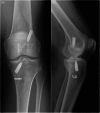

Methods: This retrospective study evaluated patients who underwent ACL revision surgery following initial reconstruction using the LARS device. Clinical assessments included the Tegner activity scale, Lysholm Knee score, and International Knee Documentation Committee (IKDC) scores, recorded preoperatively and at a minimum follow-up of 5 years. Preoperative imaging was conducted to assess tunnel widening, alignment, and the presence of arthritic changes. Intraoperative evaluations included arthroscopic inspection of the synovium, menisci, and cartilage. Synovial biopsies were obtained for histological analysis of inflammation.

Results: Twenty-five patients were included in the study. Clinical scores demonstrated significant improvement in Tegner activity scale (p = 0.0006), Lysholm Knee score (p = 0.0001) and IKDC score (p = 0.0001) following revision surgery, with a mean follow-up duration of 7.8 years (SD = 2.13). Preoperative imaging revealed early arthritic changes in 52% of patients. Intraoperative findings showed that all patients exhibited synovial membrane inflammation, with a 100% incidence of synovitis. Additionally, 68% of patients presented with Stage III or IV chondral lesions according to the ICRS classification.